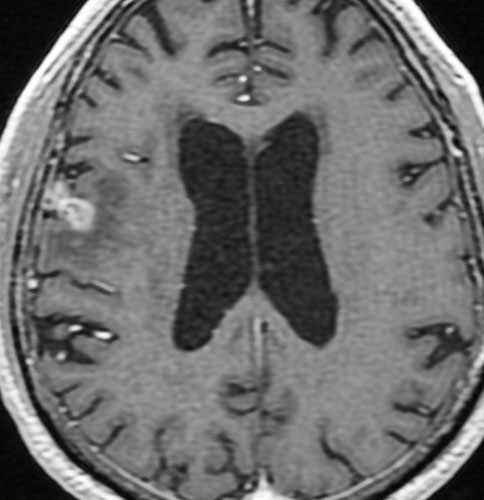

定位放射線治療後

治療は奏功して,腫瘍は縮小して周囲の脳浮腫(右側)も軽減しています。